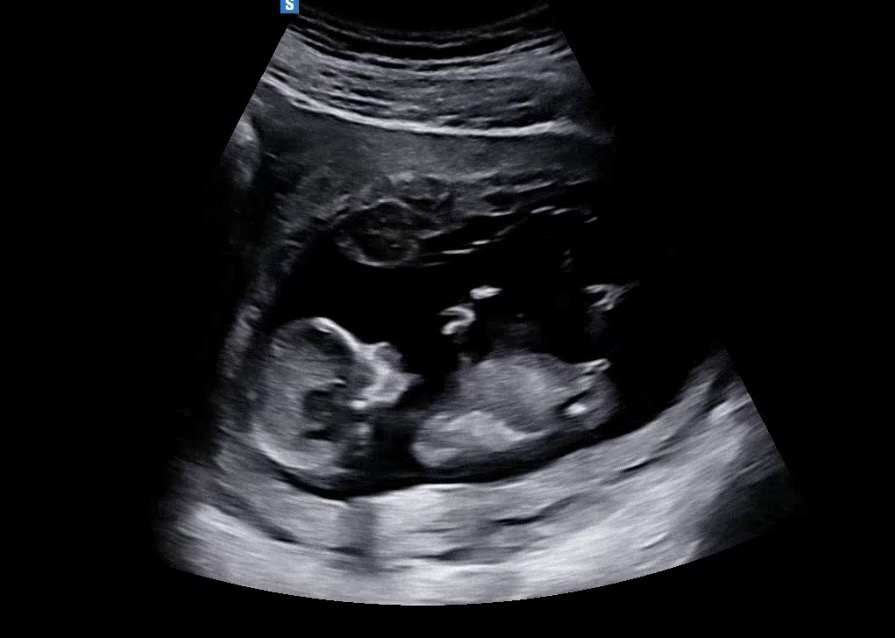

12주 3일차 각도법 성별 궁금해요!!! 제발!!

오늘 드디어 초음파 보고왔는데 각도법으로는 도저히 모르겠어요ㅜㅜ 알려주세요~~!!